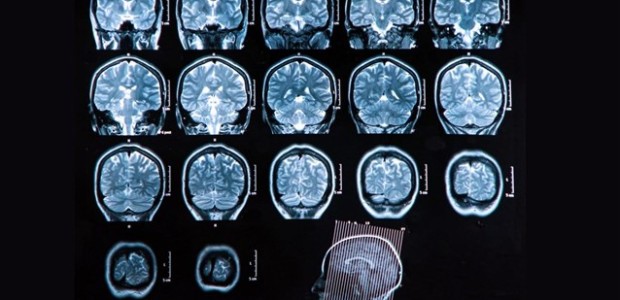

Τα ερευνητικά ενδιαφέρονται της ομάδας του Πανεπιστημίου Κρήτης εστιάζονται στην ανάπτυξη νέων συνθετικών ουσιών με νευροπροστατευτικές και νευροαναγγενητικές φαρμακολογικές ιδιότητες, με στόχο την ανάπτυξη νέων θεραπευτικών προσεγγίσεων των νευροεκφυλιστικών νοσημάτων όπως η σκλήρυνση κατά πλάκας, η νόσος του Αλτσχάιμερ ή η διαβητική αμφιβληστροειδοπάθεια.

Όπως εξηγεί ο κ. Γραβάνης, «οι συνθετικές αυτές ουσίες που ονομάσαμε μικρονευροτροφίνες μιμούνται τη δράση των νευροτροφινών, πολυτπεπτιδικών ουσιών που παράγει ο εγκέφαλος για την προστασία και ανάπτυξη των νευρώνων.»

«Ναι. Τα ερευνητικά ενδιαφέροντα της ομάδας μας εστιάζονται στην ανάπτυξη νέων συνθετικών ουσιών με νευροπροστατευτικές και νευροαναγεννητικές φαρμακολογικές ιδιότητες με στόχο την ανάπτυξη νέων θεραπευτικών προσεγγίσεων των νευροεκφυλιστικών νοσημάτων όπως η σκλήρυνση κατά πλάκας, η νόσος του Αλτσχάιμερ ή η διαβητική αμφιβληστροειδοπάθεια. Οι συνθετικές αυτές ουσίες που ονομάσαμε μικρονευροτροφίνες μιμούνται τη δράση των νευροτροφινών, πολυπεπτιδικών ουσιών που παράγει ο εγκέφαλος για την προστασία και την ανάπτυξη των νευρώνων. Πρόσφατα αναπτύξαμε στενή συνεργασία με τη διεθνή οργάνωση των ασθενών με τη νόσο του κινητικού νευρώνα ALS Worldwide και το Τμήμα Νευρολογίας και Νευροεπιστημών του Πανεπιστημίου Χάρβαρντ για τη μελέτη της αποτελεσματικότητας των μικρονευροτροφινών στη νόσο ALS, μια θανατηφόρα παραλυτική νόσο. Επιπλέον, σε συνεργασία με το Εργαστήριο Ιστιδικής Εμβιομηχανικής του Πανεπιστημίου ΜΙΤ στις ΗΠΑ και την Κτηνιατρική Σχολή του Πανεπιστημίου Κέιμπριτζ της Μ. Βρετανίας, αναπτύσσουμε τρισδιάστατα ικριώματα κολλαγόνου στα οποία καλλιεργούμε νευρικά βλαστικά κύτταρα με στόχο τη δημιουργία νευροεμφυτευμάτων για τη θεραπεία του τραύματος του νωτιαίου μυελού, καθώς και νευροαισθητήρων για την ανίχνευση νέων ουσιών με νευροαναγεννητική δράση και εφαρμογές στην ανάπλαση του γηράσκοντος ή πάσχοντος νευρικού ιστού».